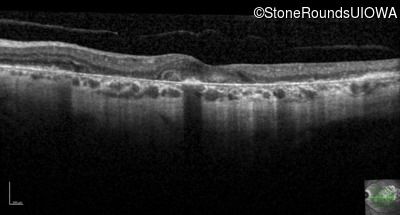

Optical Coherence Tomography - Right - 20/25

Exemplar / OCT Stack

OCT Stack